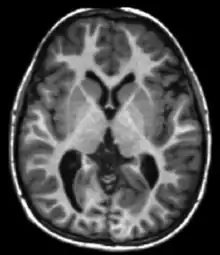

MRI is the investigative tool of choice for neurological cancers over CT, as it offers better visualization of the posterior cranial fossa, containing the brainstem and the cerebellum. The contrast provided between grey and white matter makes MRI the best choice for many conditions of the central nervous system, including demyelinating diseases, dementia, cerebrovascular disease, infectious diseases, Alzheimer's disease and epilepsy.[20][21][22] Since many images are taken milliseconds apart, it shows how the brain responds to different stimuli, enabling researchers to study both the functional and structural brain abnormalities in psychological disorders.[23] MRI also is used in guided stereotactic surgery and radiosurgery for treatment of intracranial tumors, arteriovenous malformations, and other surgically treatable conditions using a device known as the N-localizer.[24][25][26]